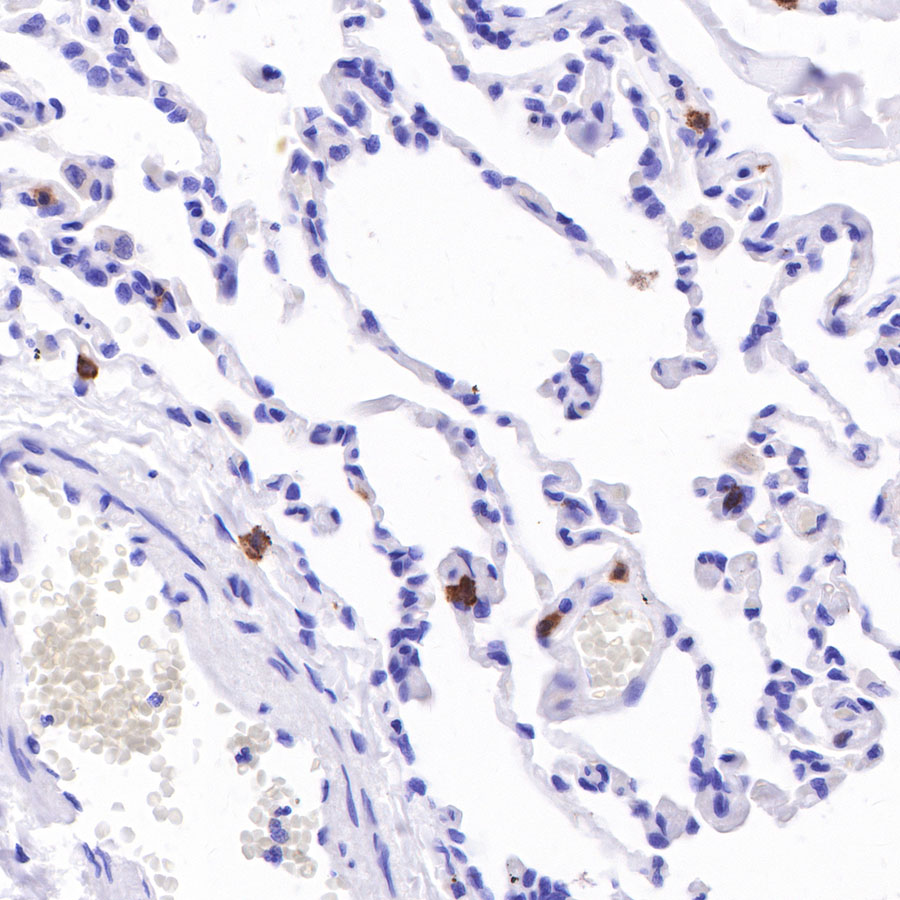

IHC shows positive staining in paraffin-embedded human lung. Anti-CD103 antibody was used at 1/100 dilution, followed by a HRP Polymer for Mouse & Rabbit IgG (ready to use). Counterstained with hematoxylin. Heat mediated antigen retrieval with Tris/EDTA buffer pH9.0 was performed before commencing with IHC staining protocol.

IHC shows positive staining in paraffin-embedded human lung squamous cell carcinoma. Anti-CD103 antibody was used at 1/100 dilution, followed by a HRP Polymer for Mouse & Rabbit IgG (ready to use). Counterstained with hematoxylin. Heat mediated antigen retrieval with Tris/EDTA buffer pH9.0 was performed before commencing with IHC staining protocol.

IHC shows positive staining in paraffin-embedded human pancreatic cancer. Anti-CD103 antibody was used at 1/100 dilution, followed by a HRP Polymer for Mouse & Rabbit IgG (ready to use). Counterstained with hematoxylin. Heat mediated antigen retrieval with Tris/EDTA buffer pH9.0 was performed before commencing with IHC staining protocol.

IHC shows positive staining in paraffin-embedded human gastric cancer. Anti-CD103 antibody was used at 1/100 dilution, followed by a HRP Polymer for Mouse & Rabbit IgG (ready to use). Counterstained with hematoxylin. Heat mediated antigen retrieval with Tris/EDTA buffer pH9.0 was performed before commencing with IHC staining protocol.